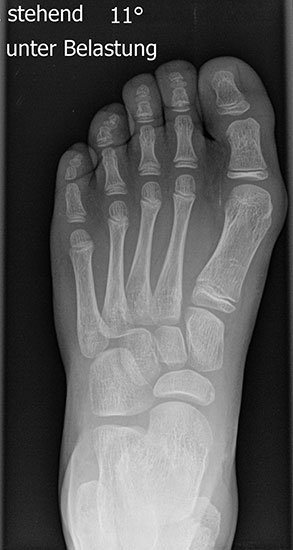

Röntgen

Standard ist die belastete Röntgenaufnahme des Fußes dorso-plantar und seitlich. Günstig ist eine Röhrenkippung von 10°-20°, um die Gelenke der Lisfranc-Linie einsehen zu können.

• Hallux valgus Winkel

• Hallux valgus interphalangeus Winkel

• Intermetatarsalwinkel I zu II

• Distaler Metatarsale Gelenkwinkel (PASA)

Tabelle 1: Normwerte der Winkelmaße

Intermetatarsalwinkel Hallux valgus Winkel

Normalwerte < 10° < 20°

Leichte –mittelgradige Fehlstellung 10°- 16° 20°- 40°

Schwere Fehlstellung > 16° > 40°